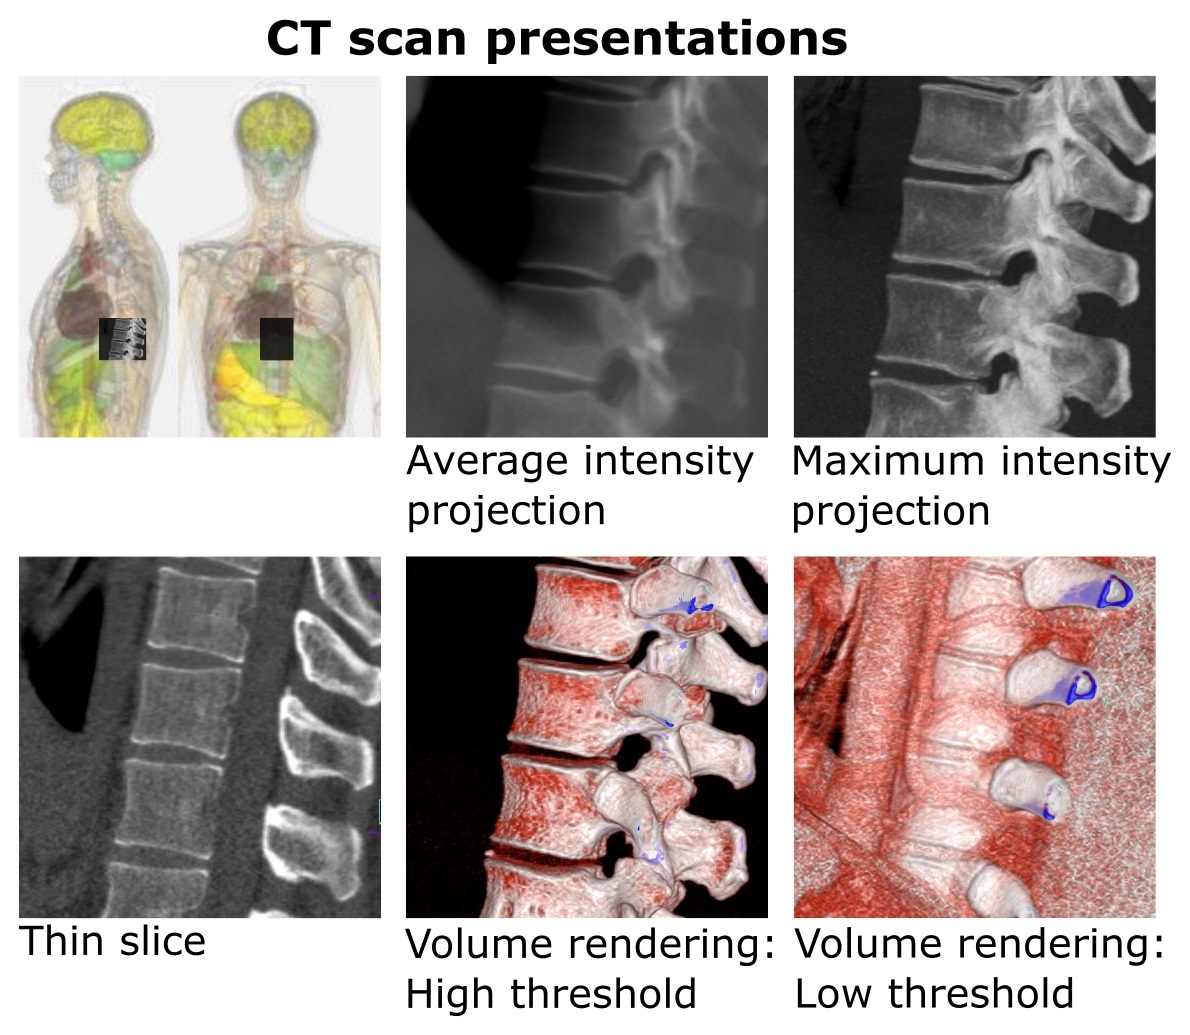

볼륨 렌더링은 얇은 단면 단층 촬영 프레젠테이션이나 최대 강도 투영을 포함한 3D 모델의 투영과는 구별된다.[1] 하지만 기술적으로 모든 볼륨 렌더링은 2차원 디스플레이에 표시될 때 투영이 되므로, 이 둘의 구분이 다소 모호하다. 그럼에도 불구하고 볼륨 렌더링 모델은 현실적이거나 관찰 가능한 표현을 만들기 위해 색상[2]과 음영[3]을 혼합하여 특징을 나타낸다.

볼륨 렌더링은 얇은 단면 단층 촬영 프레젠테이션과 구별되며, 최대 강도 투영을 포함한 3D 모델의 투영과도 일반적으로 구별된다.[1] 하지만 기술적으로 모든 볼륨 렌더링은 2차원 디스플레이에서 볼 때 투영이 되므로, 투영과 볼륨 렌더링의 구분이 다소 모호하다. 그럼에도 불구하고 볼륨 렌더링 모델의 전형적인 예는 현실적이거나 관찰 가능한 표현을 만들기 위해, 예를 들어 색상[2]과 음영[3]을 혼합하여 특징을 나타낸다.